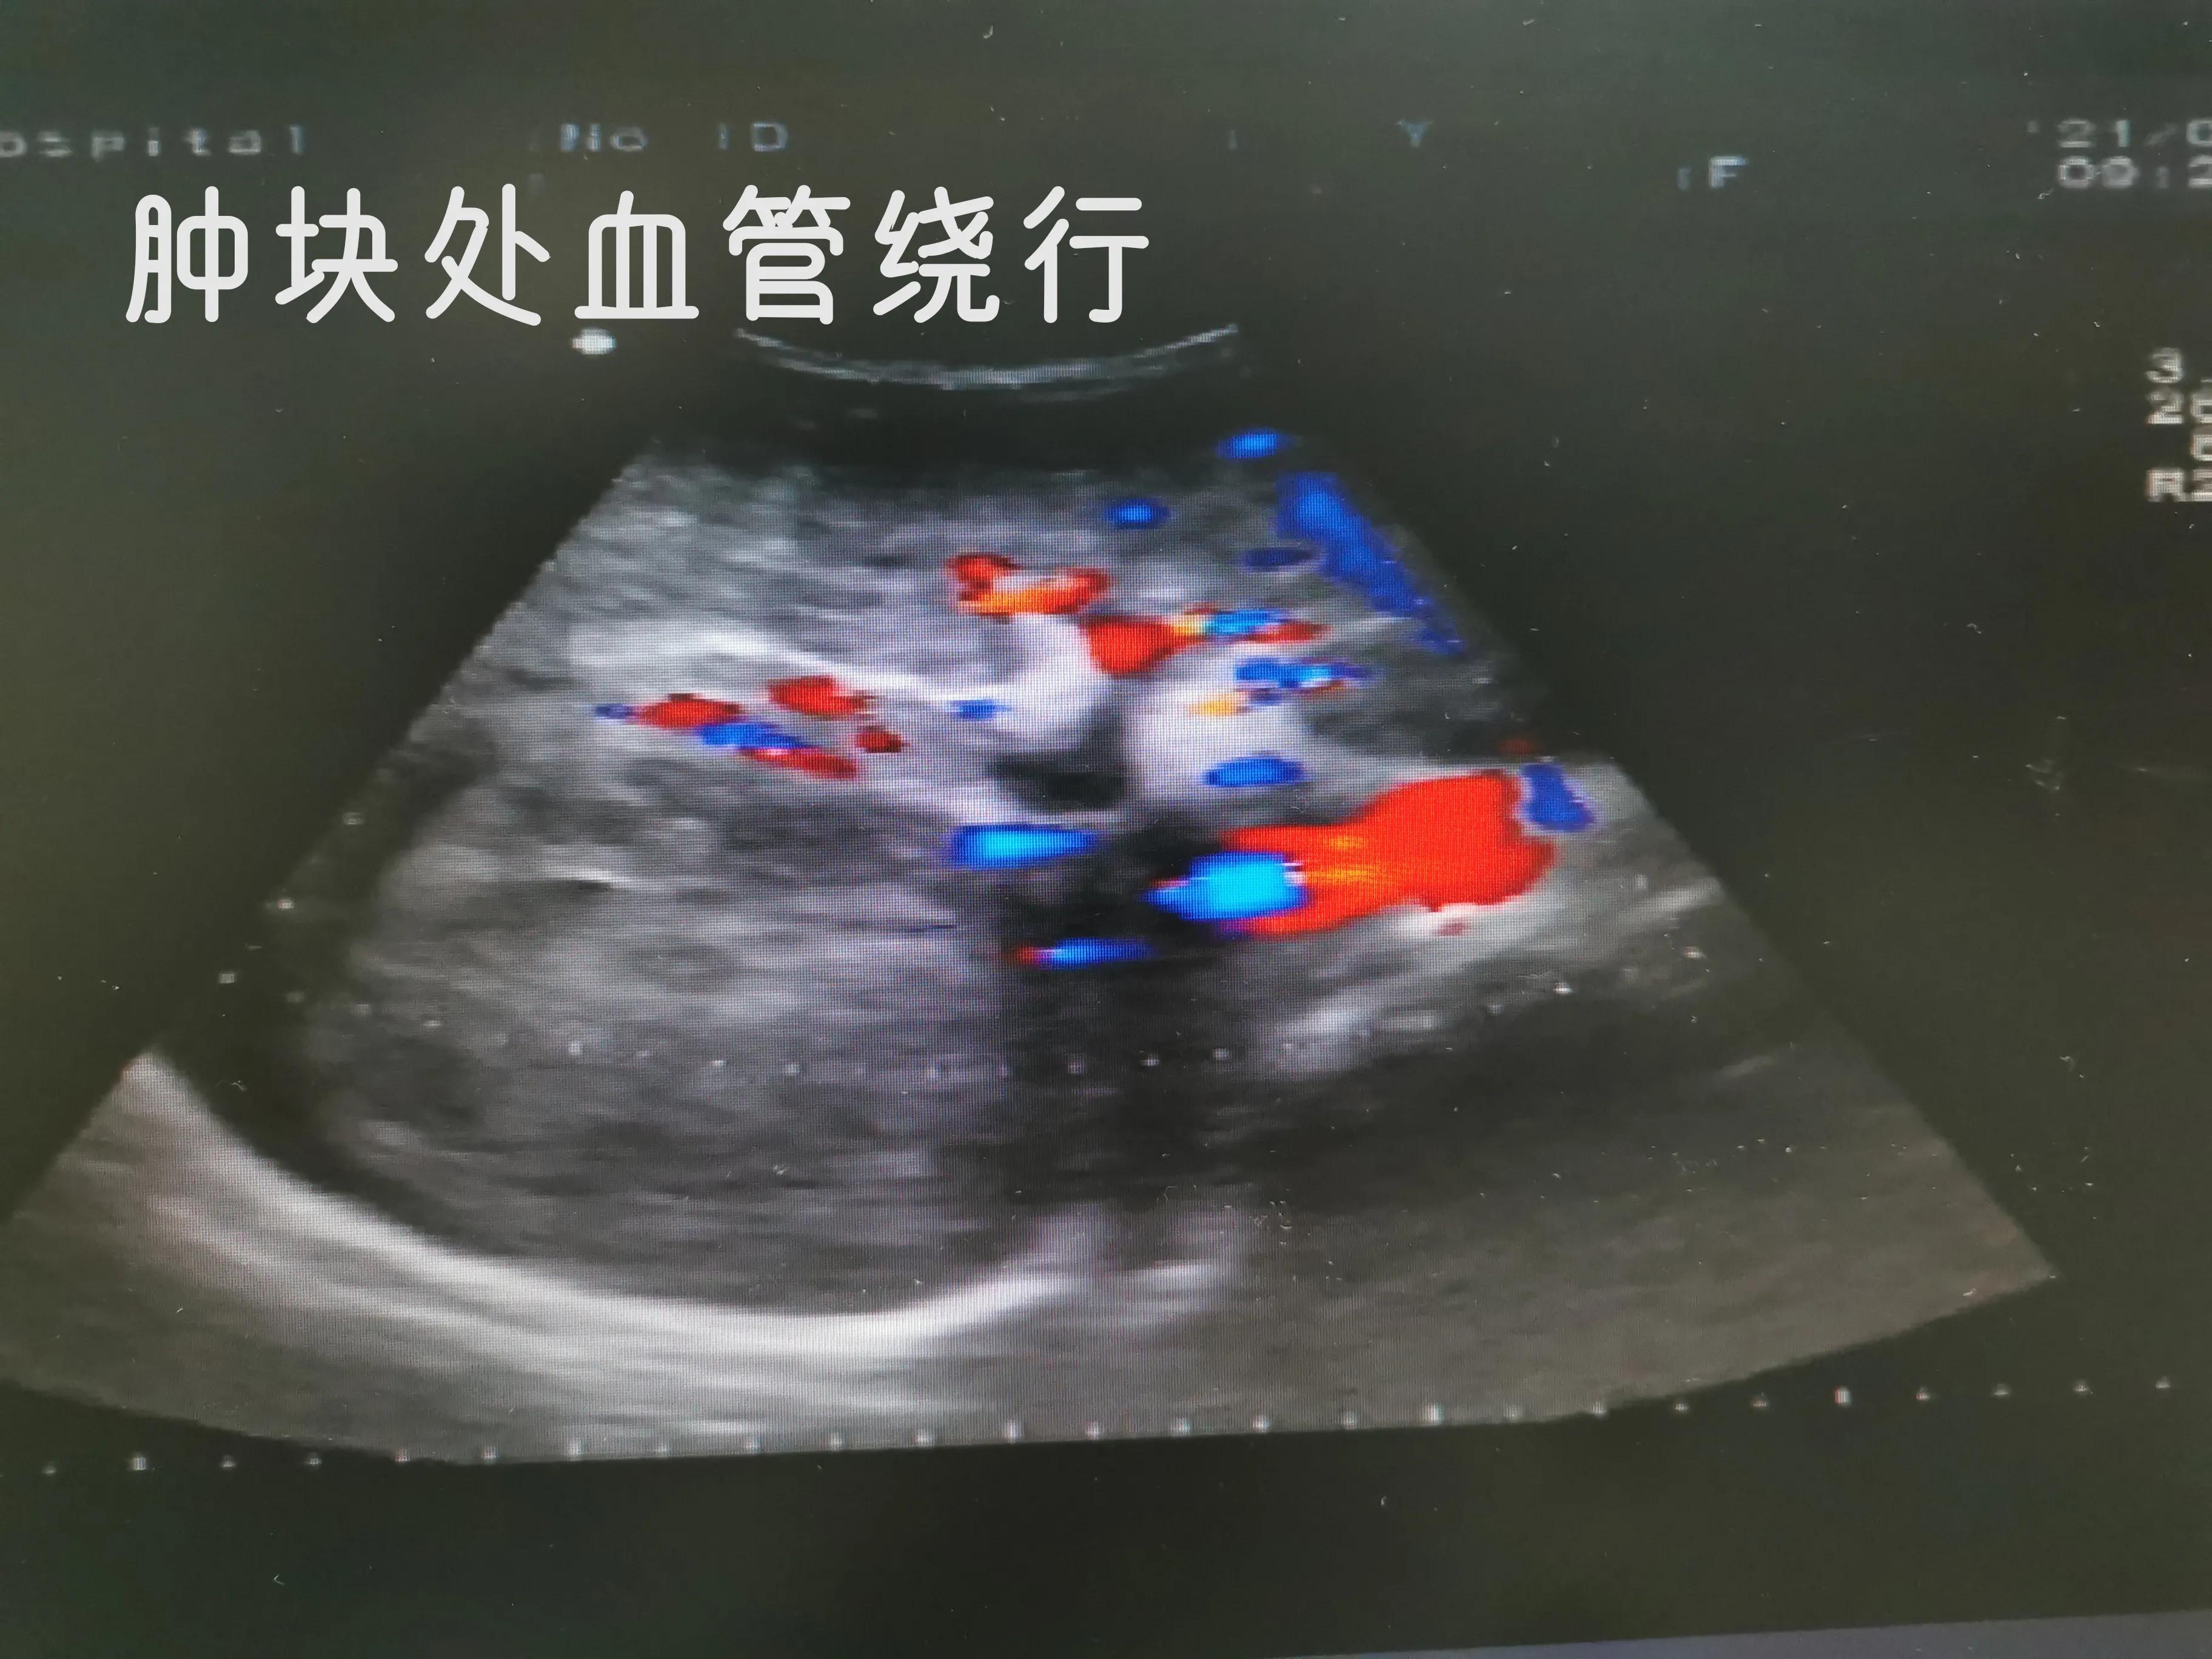

肝癌肿块

血管内癌栓形成